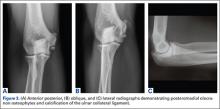

Imaging is essential to the accurate diagnosis of VEO and related conditions. Anterior posterior (AP), lateral, and oblique radiographs of elbow (Figures 3A-3C) may show posteromedial olecranon osteophytes and/or loose bodies. Calcification of ligaments or other soft tissues may also be seen. An AP radiograph with 140° of external rotation may best visualize osteophytes on posteromedial olecranon.18 A computed tomography scan with 2-dimensional sagittal and coronal reconstruction and 3-dimensional surface rendering (Figures 4A, 4B) may best demonstrate morphological abnormalities, loose bodies, and osteophytes. Magnetic resonance imaging (MRI) is essential for assessment of soft tissues and chondral injuries. MRI may detect UCL compromise, synovial plicae, bone edema, olecranon, or stress fractures.